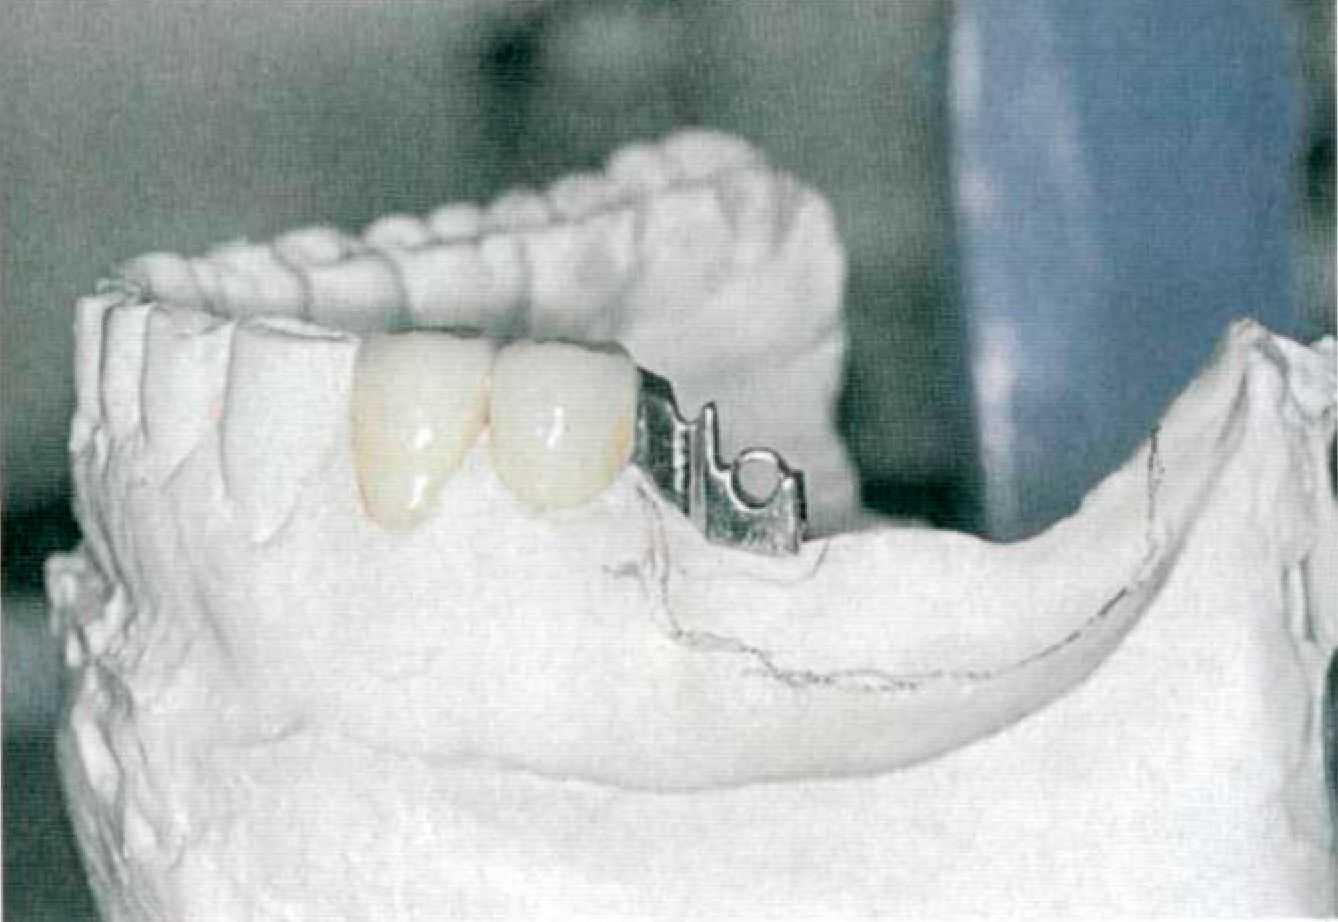

Далее снимают двухслойный или однослойный (монофазный) оттиск силиконовым оттискным материалом, препарированные зубы покрывают временными коронками (рис. 105). Определяют центральную окклюзию с формированием протетической плоскости. Этап 3. В лаборатории зубной техник изготавливает разборную модель из супергипса, гипсует модели в артикулятор и моделирует каркас коронок опорных зубов с патрицей или матрицей аттачмена, установленной в параллелометре (рис. 106). Обязательным условием при использовании жесткого замкового крепления является фрезерование опорных коронок (рис. 107).

Этап 5. После нанесения зубным техником керамической облицовки в клинике проводят припасовку металлокерамических коронок опорных зубов (рис. 109). Выверяют окклюзионные контакты, цвет. Этап 6. После глазуровочного обжига коронки фиксируют в полости рта на корригирующий оттискной материал для избежания смещения (рис. 110) и снимают оттиск для изготовления съемной части комбинированного протеза. Возможно применение индивидуальной ложки, изготовленной по предварительному альгинатному оттиску. Опорные коронки с замковыми креплениями переходят в оттиск (рис. 111). Этап 7. В лаборатории опорные коронки заливают воском и по полученному оттиску изготавливают рабочую модель (рис. 112). К замковому креплению, установленному на опорных коронках, присоединяют комплементарную часть (рис.113) или ее аналог. В зависимости от типа замкового крепления и конструкции съемной части протеза модель дублируют или проводят моделировку каркаса на рабочей модели, используя беззольную пластмассу (рис. 114).